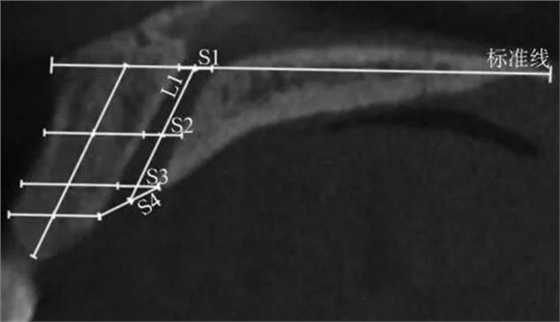

(1)正中矢狀面(圖1~3)。所使用的測(cè)量參數(shù)及其定義如下所述。鼻腭管高位直徑(S1):標(biāo)準(zhǔn)線交鼻腭管處的管徑;鼻腭管中位直徑(S2):鼻腭管長(zhǎng)軸中點(diǎn)處的管徑;鼻腭管低位直徑(S3):管后壁腭側(cè)骨最低點(diǎn)至對(duì)應(yīng)管前壁的水平管徑;切牙孔開(kāi)口直徑(S4):管后壁腭側(cè)骨最低點(diǎn)至唇側(cè)骨低位厚度和管前壁交點(diǎn)的直線距離。唇側(cè)骨高位厚度(T1):S2平面處唇側(cè)骨板水平厚度;唇側(cè)骨中位厚度(T2):S3平面處唇側(cè)骨板水平厚度;唇側(cè)骨低位厚度(T3):唇側(cè)骨最凸處骨板水平厚度。鼻腭管長(zhǎng)度(L1):S1與S4中點(diǎn)間的距離;唇側(cè)骨長(zhǎng)度(L2):唇側(cè)骨下端最低點(diǎn)經(jīng)T1、T3中點(diǎn)至標(biāo)準(zhǔn)線的直線長(zhǎng)度。鼻腭管傾斜角度(A1):L1和標(biāo)準(zhǔn)線的垂線所成角度;唇側(cè)骨傾斜角度(A2):L2和標(biāo)準(zhǔn)線的垂線所成角度。

S1:鼻腭管高位直徑;

S2:鼻腭管中位直徑;

S3:鼻腭管低位直徑;

S4:切牙孔開(kāi)口直徑;L1:鼻腭管長(zhǎng)度。

圖 1 矢狀面鼻腭管管徑測(cè)量方法

Fig 1 Measurements ofnasopalatine canal